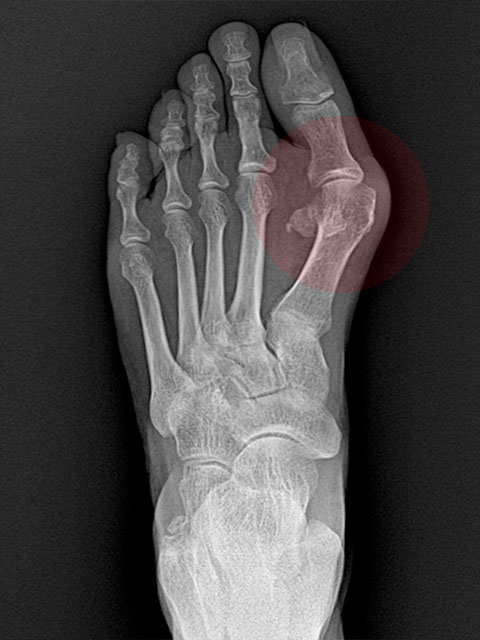

2cm

무지외반증

교정술 사례

-

Before

엄지발가락이 둘째 발가락 쪽으로 심하게 휘어 관절의 탈구가 우려되는 단계

After

심하게 꺾였던 엄지발가락의 각도가 수술 후 일자로 교정된 상태